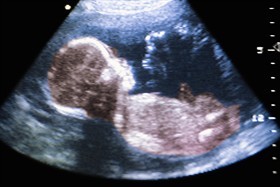

Il Governatore dell’Alabama, Robert Bentley, ha trasformato in legge un ddl sul divieto di aborto a 20 settimane (e dopo) della gravidanza. La scienza infatti dimostra che dopo questo tempo il feto prova sicuramente dolore (scappa infatti da stimoli dolorosi o cerca di difendersi con le piccole mani).

Vi rendete conto? Il feto che scappa dall’abortista? Ora capisco perché il 90% delle donne che vedono un’ecografia 4D rinunciano all’aborto, e capisco anche perché gli abortisti non vogliono diffondere questi macchinari.